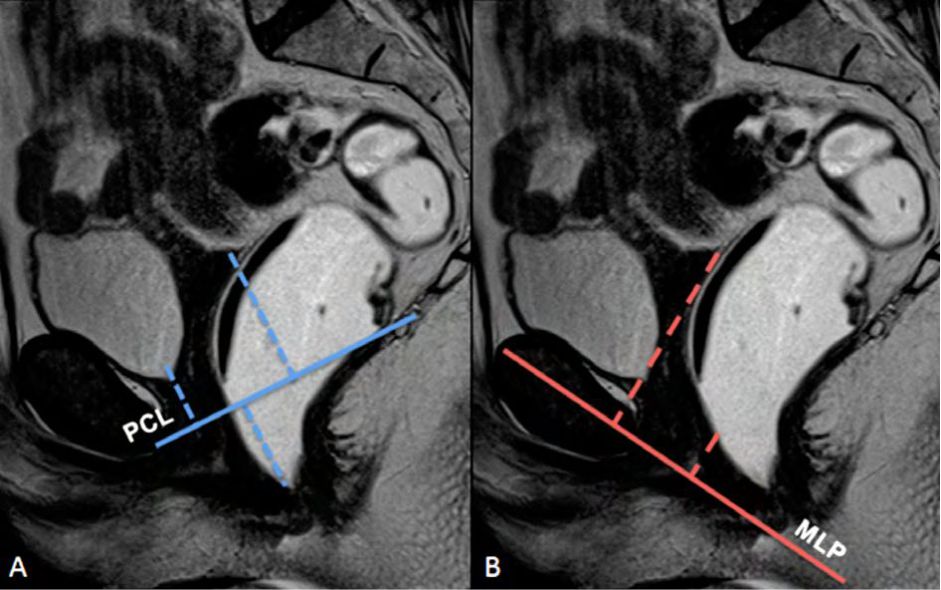

Figura 2

Líneas de referencia. Imagen de la línea media potenciada en T2 en el plano sagital, durante el reposo. Se trazaron la línea PCL (línea continua azul), línea H (línea punteada naranja) y línea M (línea punteada celeste). El músculo puborectal se topografía inmediatamente por detrás de la unión ano-rectal y el plano del elevador es paralelo a la línea PCL.

La línea H se traza desde el borde inferior del pubis hasta la pared posterior del recto a la altura de la unión ano rectal, representando el diámetro anteroposterior del hiato urogenital, con un valor normal menor a 6 cm (Ver figuras 4).

La línea M es perpendicular a la PCL a nivel del sector más posterior de la línea H y representa el descenso del hiato del elevador, con un valor normal menor a 2 cm. El ángulo ano rectal es el ángulo entre el eje central del canal anal y la pared posterior del recto, con un valor normal entre 108º y 127º y una variación de hasta 15º en Valsalva.

Figura 4

Línea H y línea M.Imágenes potenciadas en T2 de alta resolución en el plano sagital. Se observa el cambio en el valor que adopta la línea M y la línea H al comparar el reposo frente a la defecación. Según sus medidas en centímetros, se puede graduar en cuatro estadios diferentes.